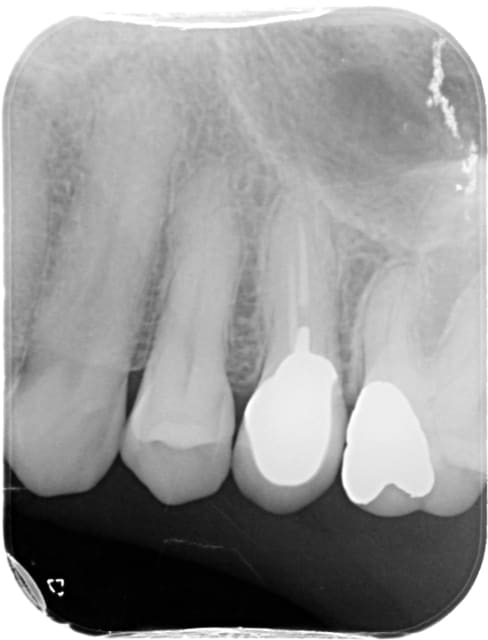

Cette patiente présente des douleurs à la percussion axiale sur la dent 15. La palpation vestibulaire est douloureuse et on peut observer une inflammation gingivale vestibulaire localisée sur 3 à 4 mm en regard de la racine de 15.

La 16 porteuse d'une grosse reconstitution à l'amg répond au froid sans problème. Et malgré l'épaississement ligamentaire sur la racine MV, la 16 ne présente aucun signe.

N'arrivant à déterminer l'origine, je suspecte une fêlure même si le tenon n'a pas l'air iatrogène vue sa taille...

... je suspecte une fêlure même si le tenon n'a pas l'air iatrogène vue sa taille...

c'est avec ce genre de tenon trop court que l'on voit des fractures/fêlures coronaires!

Radio 15/16 ou 25/26 ?? Tiens ton capteur pour une fois, et parallélise au mieux si il y a suspicion de fissure et plusieurs clichers sous différentes incidences seraient souhaitables.

26 a des signes radios.

En plus de l'élargissement, la ch pulpaire a l'air bien diminuée... Etape par étape, comme à la fac, démontage Amal 26, eugénate, tests divers et variés, phase d'observation et d'attente, les bases quoi avant de sortir l'artillerie lourde !!!

Ta radio montre un grosse obturation mésio-occlusal qui repose directement sur l'entrée du canal MV et un épaississement ligamentaire de la racine MV. Il est propable que la racine MV soit nécrosée.